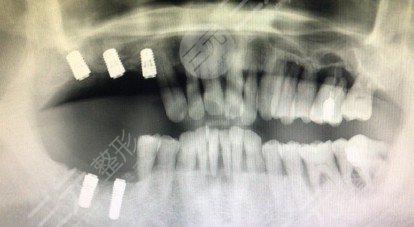

安冠全過程

隨后便是安裝了冠,這可能是全部種植階段中較痛楚的一次。成都恒泰牙科醫(yī)生把冠戴上時,我覺得明X的有疼痛感。聽他的,由于我牙床支撐力更高,牙套開啟時更疼??植赖氖怯捎诓惶醚b上,試了四五次。

擰進來后,我咬得很難受。醫(yī)師一直用紅色和藍色的“復寫紙”要我咬和打磨拋光牙套和變長的對生牙。歷經(jīng)幾十次打磨拋光,我的咬力總算越來越一切正常了!可是,我牙套的牙床是白的,成都恒泰牙科醫(yī)師要我歇息了一個小時,隨后觀查到牙床更紅了,才幫我把牙套上的小圓孔合上嘿,醫(yī)師也說十分鐘也不疼了,可是如今我的牙床還是腫的,用餐的情況下還是害怕用牙。不清楚他人是否那樣。